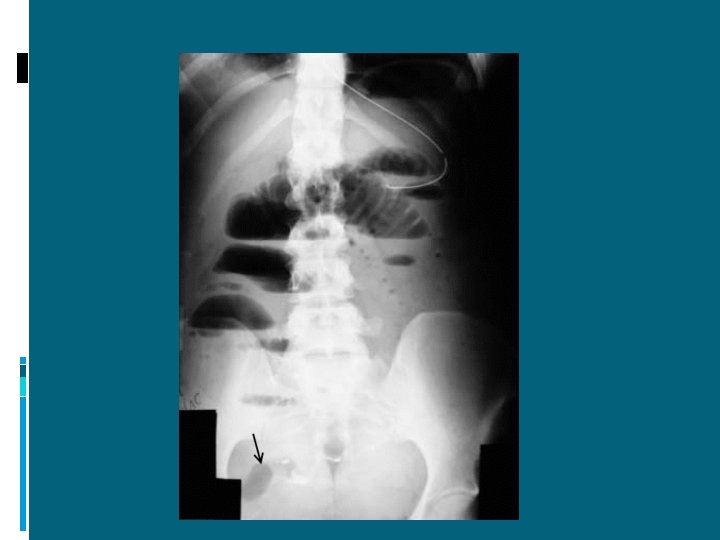

ILEO MECCANICO: DIAGNOSI RX DIRETTA ADDOME IN ORTOSTATISMO: presenza di livelli idroaerei

Perforazione di organo cavo: pneumoperitoneo

Pneumoperitoneo